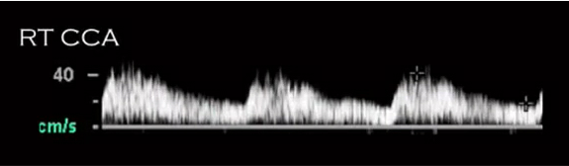

tardus parvus waveform. PROXIMAL stenosis

If shown BILATERAL parvus tardus in the carotids:

aortic stenosis